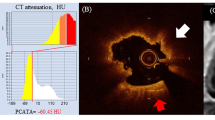

On the basis of the ROC analysis, a 3Di-PMR value of 51 PMR*mm3 was identified as the best cutoff for predicting pMI after elective PCI, with an area under the curve (AUC) of 0.753 (95% CI, 0.665–0.841). At this value, the sensitivity and specificity for predicting pMI were 74 and 76%, respectively. Table 2 and Additional file 1: Figure S4-D and S4-E show the lesion characteristics and incidence of pMI and slow flow phenomenon by 3Di-PMR cutoff value. Patients with 3Di-PMR ≥ 51 PMR*mm3 had a larger plaque volume, longer attenuation length, higher remodeling index, larger lipid volume, and higher incidence of both pMI and slow flow phenomenon than those with 3Di-PMR < 51 PMR*mm3. To show the clinical significance of 3Di-PMR, previously described predictors of pMI were compared with 3Di-PMR. From ROC analysis (Table 3), 3Di-PMR had a significantly higher AUC (0.753) than 2D-PMR (0.683 [95%CI, 0.609–0.782]) on T1w imaging (P = 0.015), as well as other IVUS or coronary angiography derived indices; attenuation length (0.641 [95% CI, 0.539–0.477], P = 0.038), remodeling index (0.547 [95% CI, 0.456–0.637], P = 0.013), and prevalence of type B2/C lesion (0.525 [95% CI, 0.438–0.613], P < 0.001), bifurcation lesion (0.612 [95% CI, 0.532–0.692], P = 0.039), and calcification (0.503 [95% CI, 0.436–0.570], P < 0.001). Figure 3 shows the correlation between 3Di-PMR and IVUS derived indices. 3Di-PMR was significantly positively correlated with total plaque volume and lipid volume (r = 0.449, P < 0.001 and r = 0.426, P < 0.001, respectively).

Correlation between 3D integral (3Di)-plaque to myocardial signal intensity ratio (PMR) and plaque characteristics based on integrated backscatter intravascular ultrasound. Correlation between 3Di-PMR and total plaque volume (a), lipid plaque volume (b), fibrous plaque volume (c), and calcified plaque volume (d) are shown